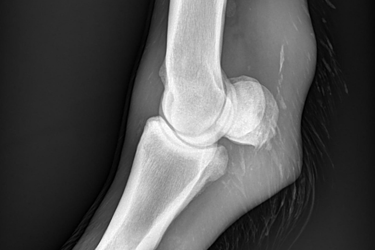

Is uw paard mank, hoefbevangen of is er een vermoeden van een halsprobleem? Dan kan het aangewezen zijn om een radiografisch onderzoek (RX) aan huis uit te voeren. Wij beschikken over een digitaal mobiel radiografietoestel, waardoor opnames eenvoudig bij u ter plaatse kunnen worden gemaakt.

Wij maken geen radiografische opnames in het kader van een radiografische keuring.

Dit onderzoek wordt uitgevoerd binnen een straal van 20 km rond de praktijk.

Radiografie (RX)

Consult op de praktijk of aan huis